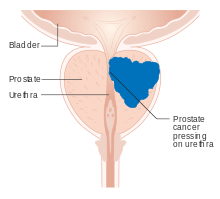

Benign prostatic hyperplasia

Benign prostatic hyperplasia (BPH) occurs in older men;[25] the prostate often enlarges to the point where urination becomes difficult. Symptoms include needing to urinate often (frequency) or taking a while to get started (hesitancy). If the prostate grows too large, it may constrict the urethra and impede the flow of urine, making urination difficult and painful and, in extreme cases, completely impossible.

BPH can be treated with medication, a minimally invasive procedure or, in extreme cases, surgery that removes the prostate. Minimally invasive procedures include transurethral needle ablation of the prostate (TUNA) and transurethral microwave thermotherapy (TUMT).[26] These outpatient procedures may be followed by the insertion of a temporary prostatic stent, to allow normal voluntary urination, without exacerbating irritative symptoms.[27]

The surgery most often used in such cases is called transurethral resection of the prostate (TURP or TUR). In TURP, an instrument is inserted through the urethra to remove prostate tissue that is pressing against the upper part of the urethra and restricting the flow of urine. TURP results in the removal of mostly transitional zone tissue in a patient with BPH. Older men often have corpora amylacea[28] (amyloid), dense accumulations of calcified proteinaceous material, in the ducts of their prostates. The corpora amylacea may obstruct the lumens of the prostatic ducts, and may underlie some cases of BPH.

Cancer

Prostate cancer is one of the most common cancers affecting older men in developed countries and a significant cause of death for elderly men[31] (estimated by some specialists at 3%). Despite this, the American Cancer Society's position regarding early detection is "Research has not yet proven that the potential benefits of testing outweigh the harms of testing and treatment". They believe "that men should not be tested without learning about... the risks and possible benefits of testing and treatment" which should be discussed with a doctor at age 50 or at age 45 if the patient is black or has a father or brother who acquired prostate cancer before age 65.[32] If checks are performed, they can be in the form of a physical rectal exam, measurement of prostate specific antigen (PSA) level in the blood, or checking for the presence of the protein Engrailed-2 (EN2) in the urine.